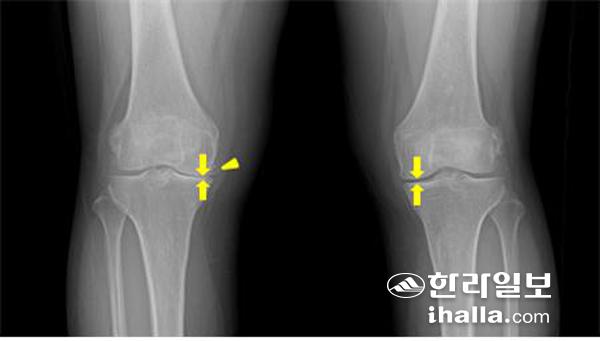

무릎관절 X-ray 사진. 관절강협착(화살)과 골극(화살머리),

골관절염의 경우 대부분 검사 없이도 병력과 임상징후만으로도 진단할 수 있지만 신체검사 소견과 영상검사결과가 일치하지 않는 경우가 있어 임상 소견이 중요하며 검사실 검사와 영상검사들을 종합해 진단한다. 단순 방사선 사진이 가장 유용한데 초기에는 정상 소견을 보일 수 있으나 점진적으로 관절 간격의 감소가 나타나며 연골 아래 뼈의 음영이 짙어지는 경화 소견을 볼 수 있다. 더욱 진행되면 관절면의 가장 자리에 뼈가 웃자란 듯한 골극이 형성되고 관절면이 불규칙 해진다.